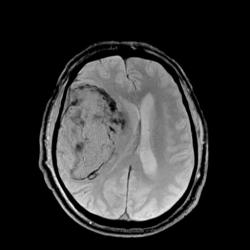

Наличие крови наиболее четко видно на T2* GRE импульсной последовательности.

Наличие крови наиболее четко видно на T2* GRE импульсной последовательности.

Гематому в данном случае с головой выдает периферическая полоска, окружающая образование с гипоинтенсивным (особенно на GRE ИП) МР сигналом. Иначе чем еще ее можно объяснить?

А периферическая гипоинтенсивная полоска вокруг гематомы - это отек?

Нет, отек - это гиперинтенсивный сигнал вокруг гематомы. С течением времени он буден нарастать.

А гипоинтенсивная полоска - это проявления начинающегося распада гемоглобина (метгемоглобин).

в данном случае все рано нужен динамический МР контроль, для исключения кровоизлияния на фоне объемного процесса, гематома имеет определенные эвоюлюционные призанакив зависимости от стадии.

К сожалению, проведение динамического контроля в данном случае невозможно, т.к. поражение оказалось несовместимым с жизнью.

В данном случае это классический геморрагический инсульт. По моему опыту с таким смещением срединных структур как на представленных МР-томограммах нейрохируги редко берут на операцию - благополучный постоперационный прогноз маловероятен, да и большиноство пациентов погибают за считанные часы, многие на операционном столе. Евгений, наверное, узнает у пат.анатомов результат вскрытия и напишет нам уже верифицированный диагноз.